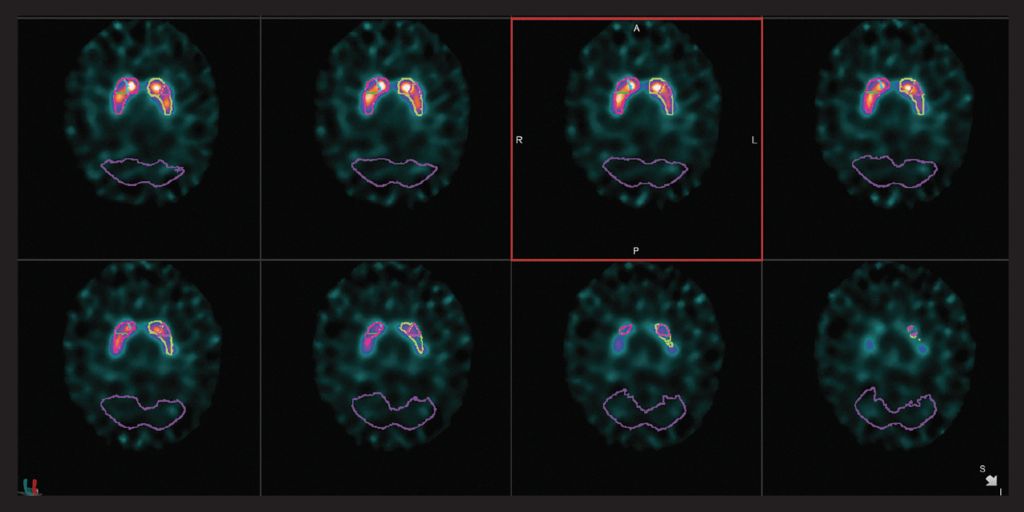

心臟

VERITON ? 采用我們成熟的CZT探測(cè)器技術(shù),可實(shí)現(xiàn)更好的協(xié)議優(yōu)化??紤]使用如此處所示的標(biāo)準(zhǔn)劑量的高分辨率2分鐘MPI采集,或選擇顯著更低的劑量同時(shí)保持短的采集時(shí)間。通過(guò)擴(kuò)展示蹤劑使用來(lái)檢查增加未來(lái)心臟實(shí)踐的方法。